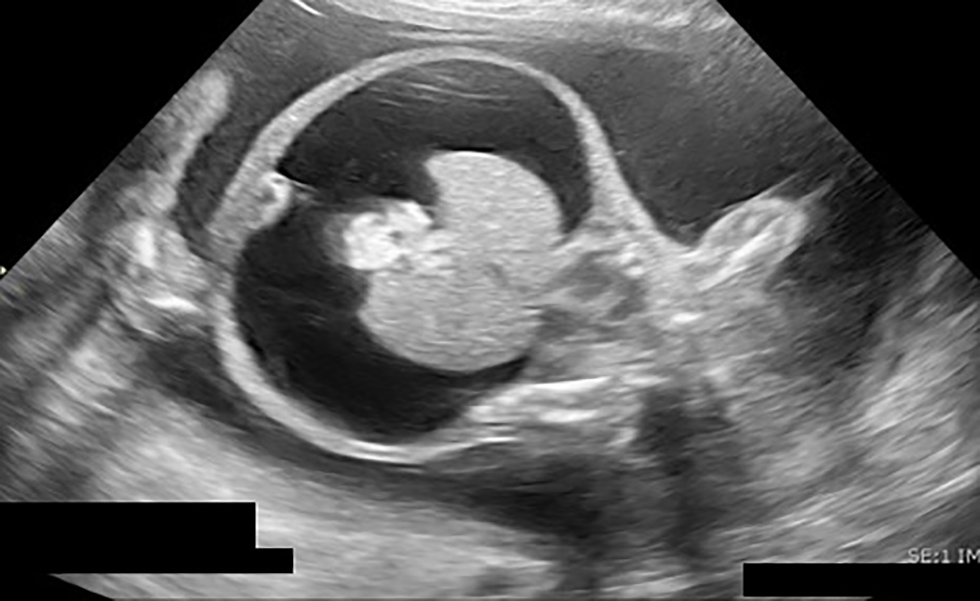

Ultrasound performed by Maternal Fetal Medicine demonstrated a single live intrauterine pregnancy at gestational age of 19+3 weeks. The fetus was affected by severe hydrops fetalis, as demonstrated by large pleural effusions, large ascites compressing the kidneys and body wall edema (Figure 1). The brain was very abnormal with bright cerebrospinal fluid and streaky echoes throughout the cortex (Figure 2). There was polyhydramnios with a maximum vertical pocket of 8 cm, with a thickened and overtly hydropic placenta (Figure 3). The umbilical artery Doppler ultrasound was abnormal with an increased systolic to diastolic ratio; however, the middle cerebral artery (MCA) Doppler did not demonstrate evidence of fetal anemia (peak systolic velocity 1.37 MoM). To complete the evaluation for hydrops, amniocentesis was performed and sent for microbiologic and genetic evaluation. Results are summarized in Table 2 and were notably positive for T. pallidum on PCR testing.

Figure 1: Very large ascites, echogenic clumped bowel, compressed kidneys suggestive of high intra-abdominal pressure at 19+3 weeks gestational age

Text description: Figure 1

Ultrasound image, taken at gestational age of 19+3 weeks. Cross-sectional abdominal view, demonstrating very large ascites, echogenic clumped bowel and compressed kidneys, which suggests high intra-abdominal pressure.